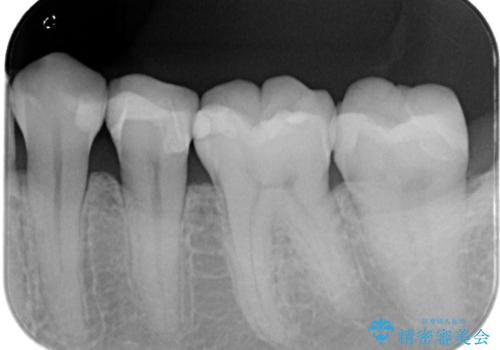

- 主訴:下の歯に入っている銀歯が笑うと目立つので白くしたい。

下顎臼歯部に入っている保険適用のメタルインレー(4箇所)を、審美性・適合性・清掃性の良いセラミックインレーにてやり替えました。